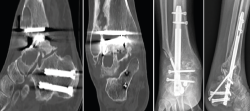

Figura 3. Imágenes del clavo tibiotalocalcáneo roto a través de la trinchera ósea y maniobra de extracción con guías endomedulares ayudadas por la impactación directa en la muesca realizada en el clavo.

Se reintervino al paciente realizando la extracción del fragmento distal del clavo con el sistema extractor del mismo. Para la extracción del extremo proximal fue necesario, además de la utilización de las guías curvadas, abordar el foco de la pseudoartrosis hasta visualizar el clavo y, con una fresa de alta velocidad, hacer una muesca en el mismo. Mediante la percusión sobre un escoplo apoyado en la muesca realizada en el clavo y con la ayuda de las agujas guía introducidas a través del clavo, se consiguió la extracción del extremo proximal a través de la planta del pie (Figura 3). Se legró la superficie articular tibiotalar y se colocó injerto de cresta ilíaca, fijando la artrodesis con una placa TTC (Palex Medical), aunque la articulación subtalar estuviese artrodesada, para dar mayor solidez al montaje.